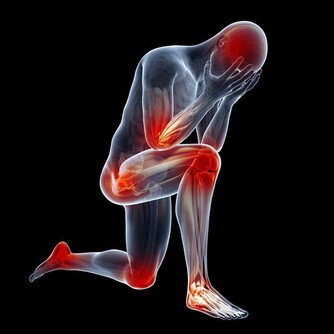

日常生活中,人們以酒待客,既能體現主人的禮儀和熱情,也能放鬆情緒,拉近彼此感情距離,適量飲酒還能起到舒筋活血,禦寒,消除疲勞,促進消化等作用。

酒精對身體的危害十分廣泛包括心腦血管、中樞神經、消化系統、肝膽脾胃等,我下面著重介紹一下不大多見,與酒密切相關一種病,馬德龍病。